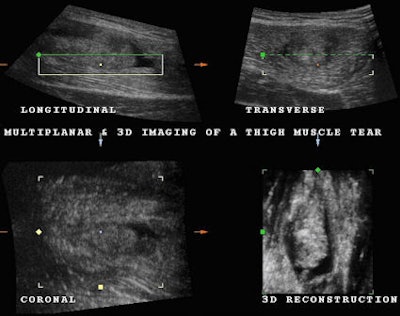

Fig. 1: Longitudinal plane demonstrating a distal aponeurosis tear. Note the retracted rounded end of the muscle and the presence of a distal hematoma (black area). All images courtesy of Dearbhla O'Dwyer and Dr. Stefano Ciatti.Once the location of the tear was determined, we decided to perform a 3D volume acquisition to better study the condition of the muscle and the full extent of the tear. Three-dimensional volume acquisition permits one to scroll backward and forward and up and down through the acquired volume.

The coronal plane permits a frontal view traditionally unavailable in ultrasound scanning that frequently allows a better appreciation of the extent of a tear (Fig. 2). As with many modern imaging modalities, 3D reconstruction is used to demonstrate both normal and abnormal anatomy. In this particular case, the complete separation of the muscle fibers from the point of insertion is well demonstrated along with a large hypoechoie fluid collection and coagulation material with the use of the coronal plane and 3D reconstruction (Fig. 3 and 4).

Fig. 2: Coronal plane clearly demonstrating the retracted muscle fibers with a swollen blunt end as a result of avulsion and surrounding hematoma. We noted a small quantity of coagulation material distally and deep to the tear.

Fig. 3: Using multiplanar imaging and 3D reconstruction, it is possible to confirm the presence of the muscle tear at the level of the distal aponeurosis surrounded by hematoma or hypoechoic tissue related to hemorrhagic infiltration and coagulated material.